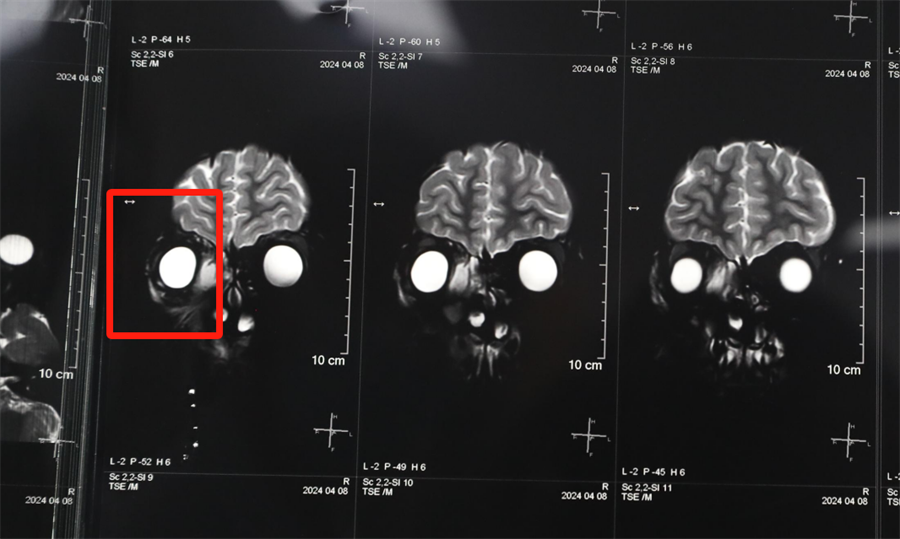

经眼科、耳鼻喉科联合会诊,医生发现孩子是因为患了急性鼻窦炎,导致右眼急性细菌感染,确诊为“右侧眶蜂窝织炎、眶内脓肿”。考虑到此病进展较快,可能导致视力下降甚至失明,耳鼻喉科立即将患儿收治入院。静脉输液、对症支持治疗、密切监测视力变化,一切有条不紊。入院第2天,孩子自觉右眼视力下降明显,眼科紧急会诊发现,其右眼视力从患病前的1.0下降到0.4。

北京儿童医院常驻专家、德州扑克游戏网 副院长杨小健决定立即手术治疗引流眶内脓液,并组织多学科联合会诊。考虑到患儿年龄较小,杨小健副院长决定采取内镜经鼻腔手术引流脓液,这种手术方式创伤小、恢复快、效果确切,而且避免了外切口瘢痕,不需要反复进行局部消毒换药。但是孩子鼻腔解剖结构本身就狭窄,而且处于急性感染期,术中出血风险较大,手术难度较高,对麻醉技术也有着很高的要求。

最终,杨小健副院长熟练地将手术器械通过小小的鼻孔,伸入到曾被公认为“手术禁区”的眶鼻交界区。一个多小时后,她成功地将眼眶脓肿充分引流出来。术后,医院多学科团队密切观察患儿病情变化,每日查房讨论并及时调整治疗方案。最终,通过全体医护人员的共同努力,患儿术后第3天右眼斜视就消失了,视力也恢复到了1.0。术后5天,患儿高高兴兴地出院了。